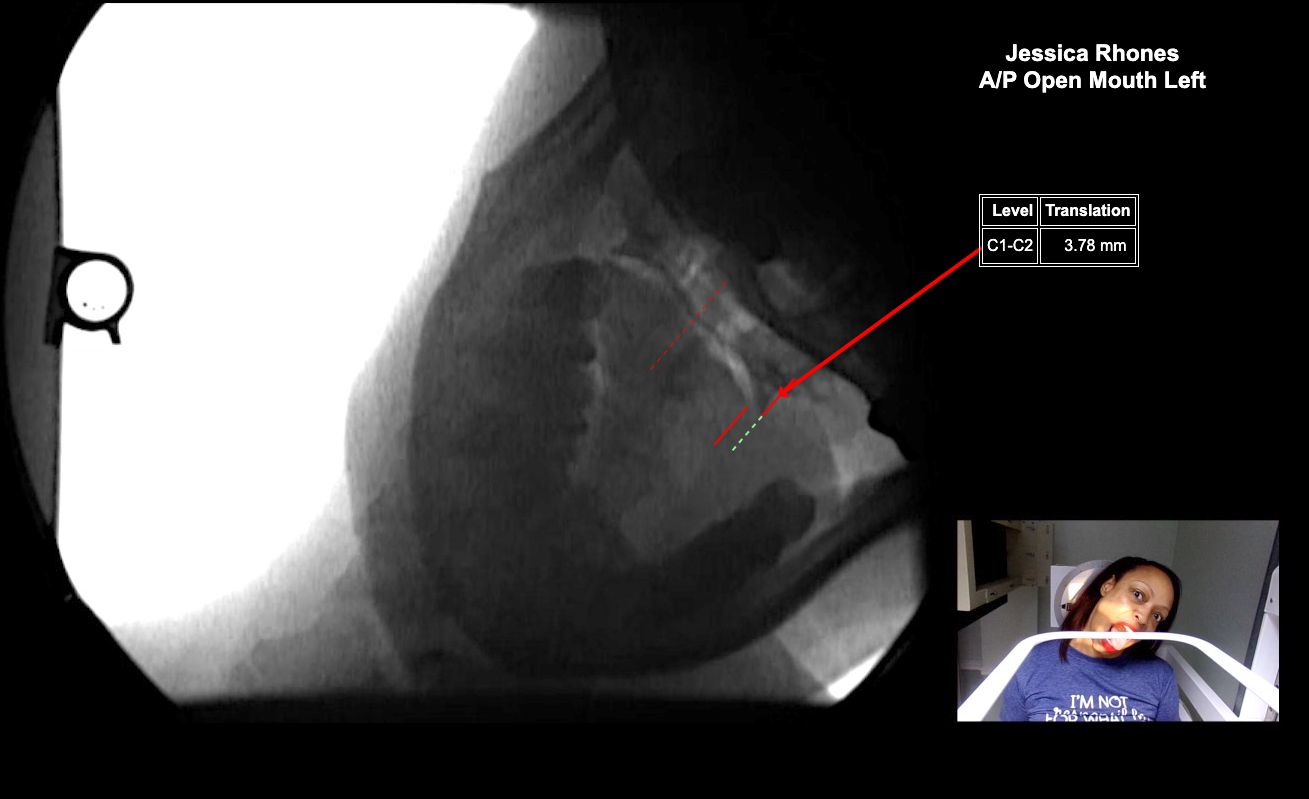

Image 2